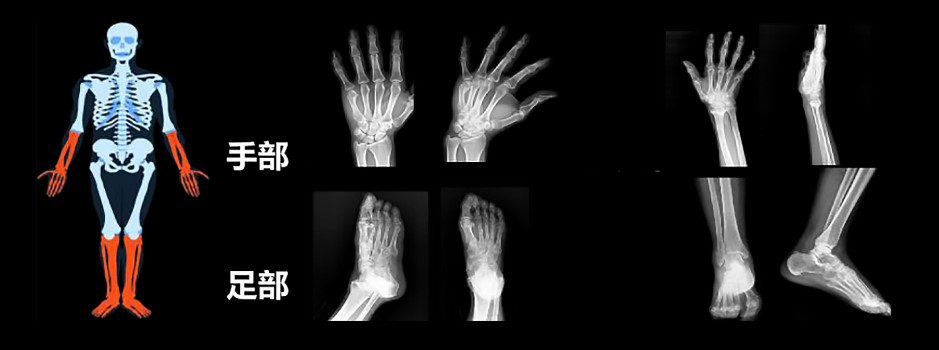

經人工智能檢測,可以清晰地看到骨骼移位的位置。

AI提高體檢骨密度篩查質量

目前,內地AI骨密度軟體已經在很多醫院落地。據介紹,這款軟體能夠在28秒內就完成骨密度篩查的初步分析。現在內地很多體檢中心採用四肢的X光骨密度或超聲測量做體檢,這些檢查方法只能用於篩查,不能用於診斷。「我們經常會碰到,在體檢時檢查手指的骨密度,報告骨質疏鬆,但跑到醫院做了DXA檢測,再做QCT檢測,最後結果是骨密度正常。」很顯然,如果能做DXA或QCT檢查更有優勢。AI的引入,或許能提高體檢骨密度篩查的品質。從現在的對照結果來看,AI骨密度軟體的檢測精確度,與QCT的檢測結果相比能夠達到99%的一致性。